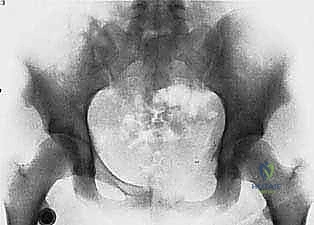

- Plain Radiography (FIG 2): While of limited value for early lesions, it provides an initial overview. As you can see in Figure 2A, we have a large lytic lesion of the right periacetabular region. Figure 2C shows a cartilage-forming lesion in the left ilium. However, plain films often underestimate the true extent of these tumors.

* CT with Intravenous Contrast and 3D Reconstruction (FIG 3): This is our workhorse for assessing bone involvement, destruction, and the critical relationship between the tumor and major pelvic blood vessels. It reveals any distortion of the pelvic anatomy and guides resectability. Figure 3A clearly shows extensive bone destruction and tumor extension into the pelvis and gluteal region. Figure 3C highlights an extensive tumor on the medial aspect of the ilium with destruction of the inner table.